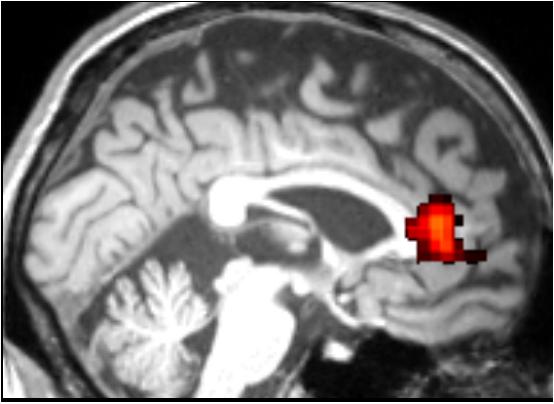

WASHINGTON (Nov. 17, 2015) -- Neuroscientists at Georgetown University Medical Center have found in a small study that although a group of HIV+ older individuals scored "cognitively normal" in standard neuropsychology testing, a scan of their brains tells a different story.

Published Nov. 17 in the journal AIDS Care , functional MRI (fMRI) scans, taken while participants were performing an alternating face-gender/word-semantic task, revealed that HIV+ individuals in the study showed deficits in cognitive functioning, compared to an age matched healthy controls.

The HIV+ group was significantly slower in adjusting to change in tasks, which correlates with brain dysfunctions in the dorsal anterior cingulate cortex (dACC), one of the key executive regions. This collar-shaped area is near the front of the brain, and damage to this region has been linked to many cognitive impairments, including executive deficits and apathy.

"Intriguingly, both impairments are highly prevalent in individuals with HIV-infection, suggesting dACC might be one of commonly affected brain regions in HIV and a potential neural target for therapies," says Jiang.